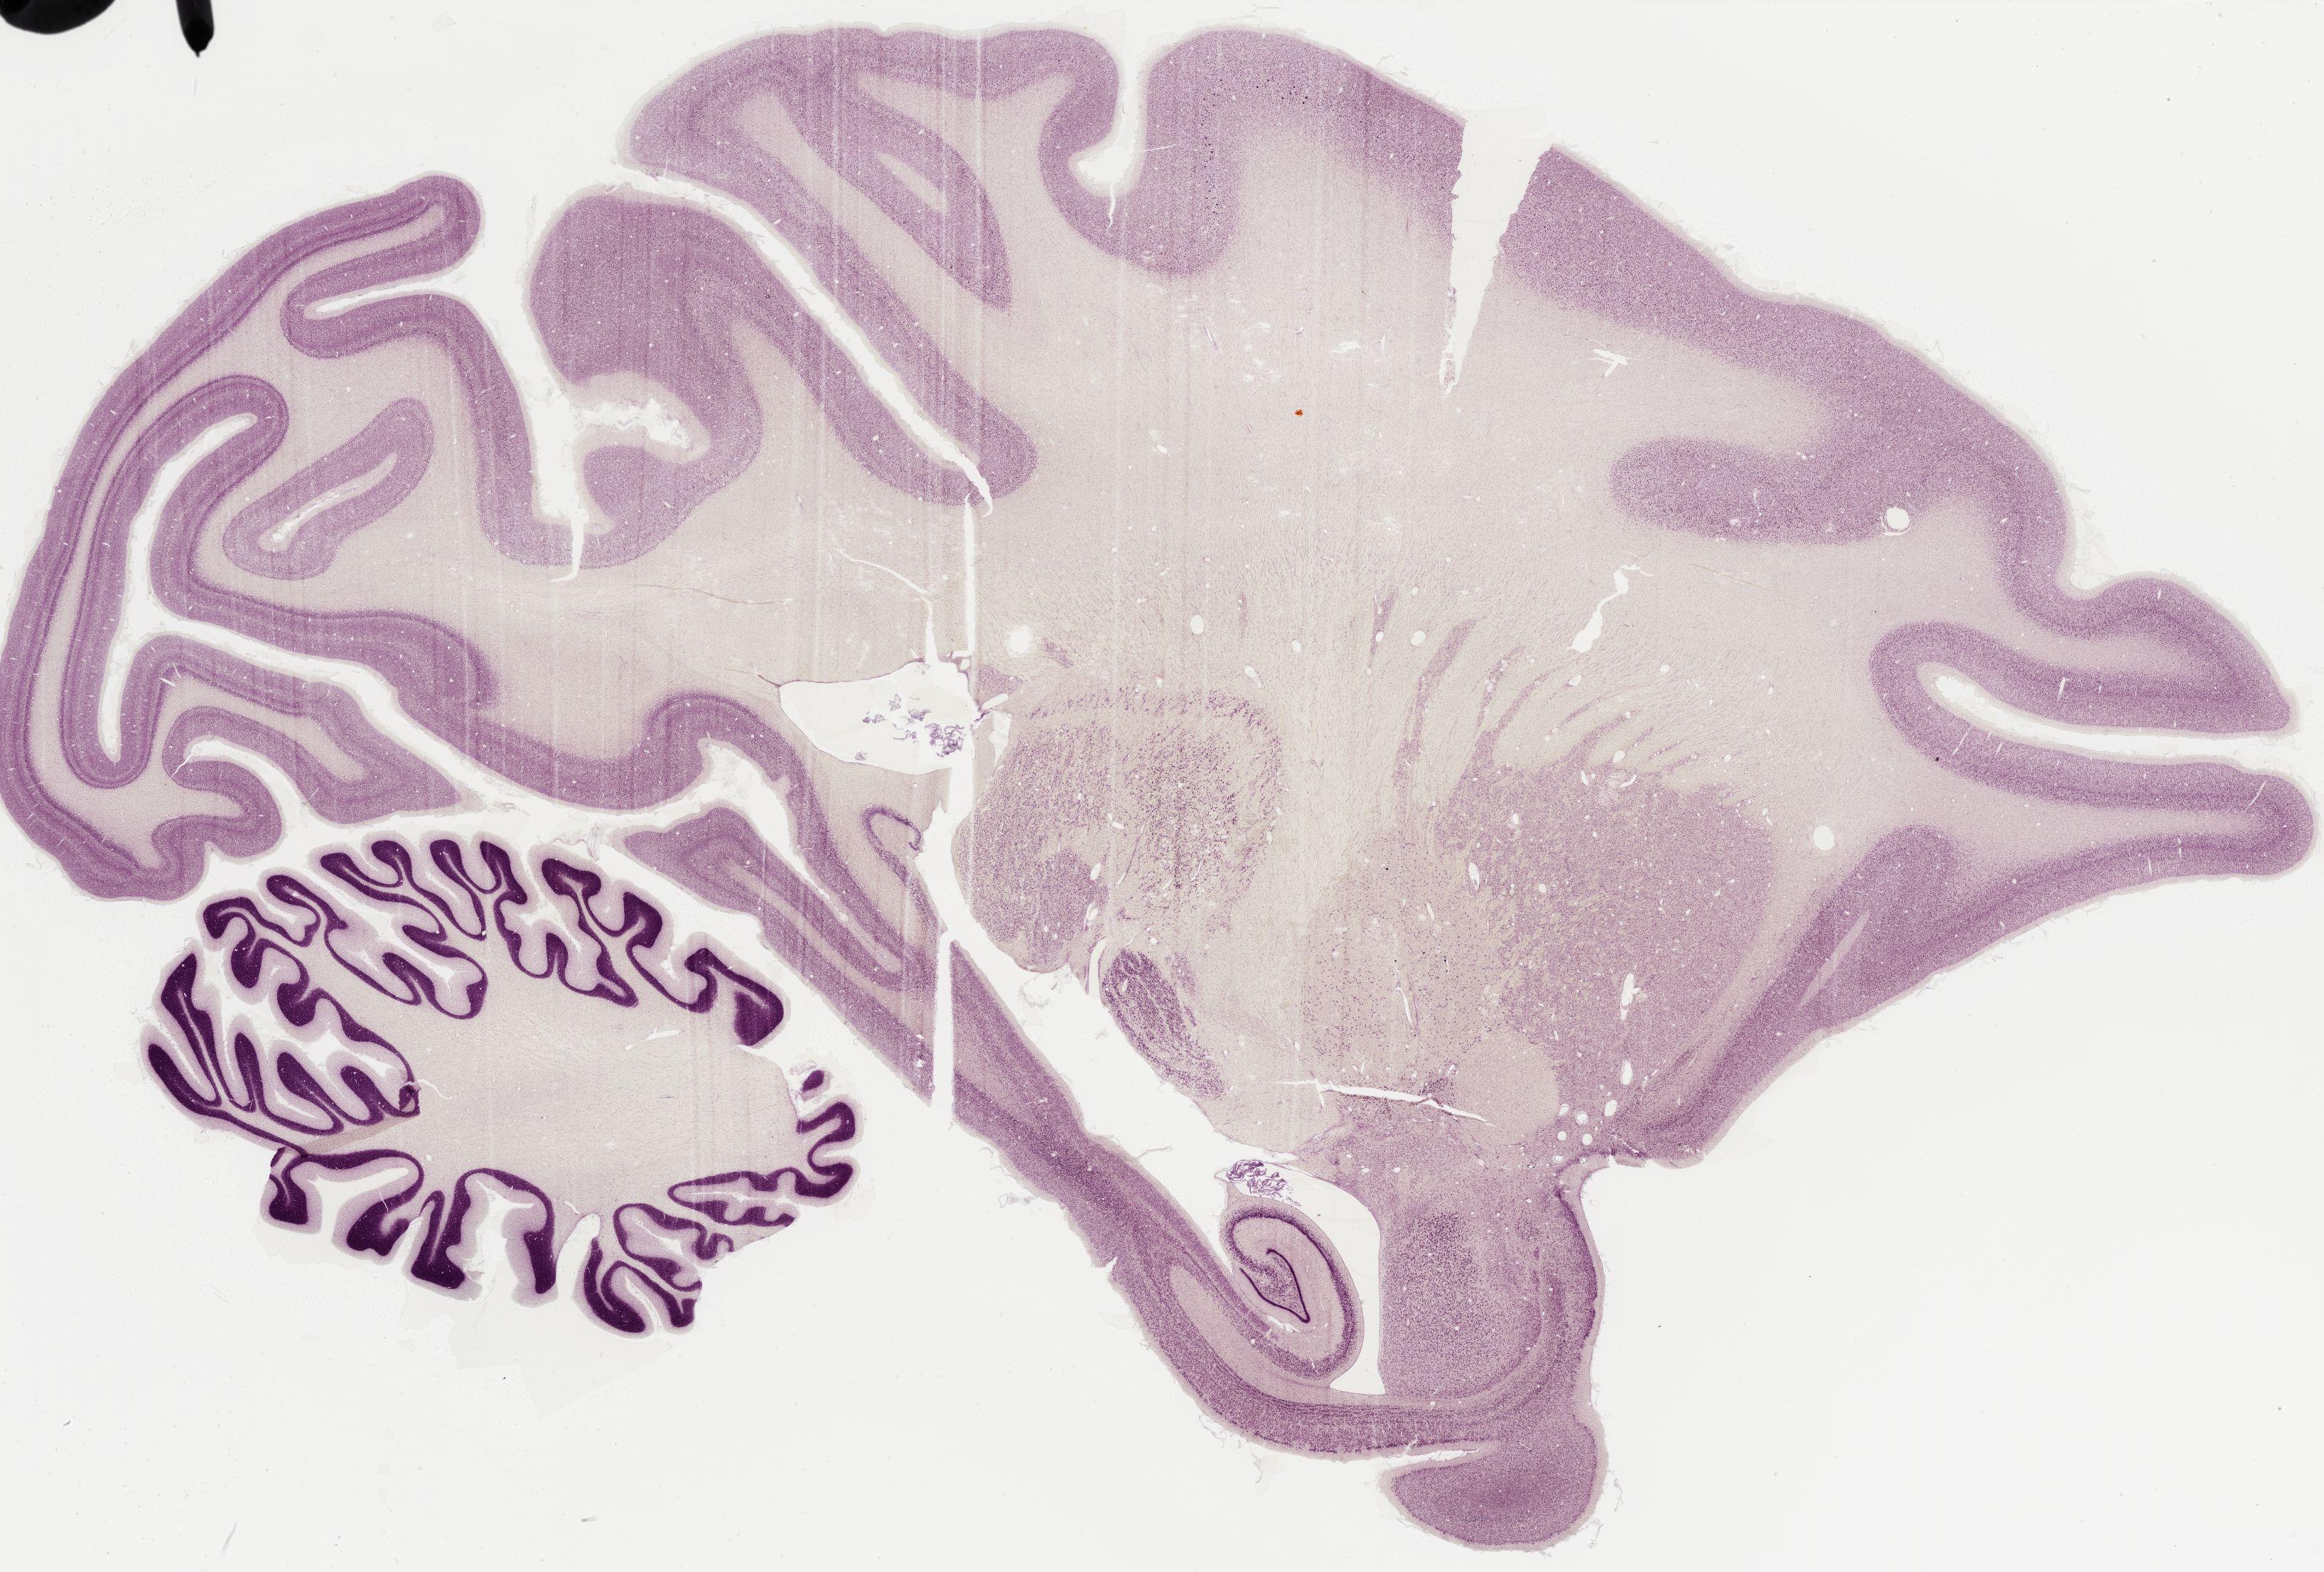

Datasets -> Macaca Mulatta -> Nissl, sagittal, histo, Whole-Brain, adult

[ Metadata ]   ·   Source: Edward G. Jones

Displaying Sections 161 thru 200 of 295 Sections for this Dataset

0366 - labeled